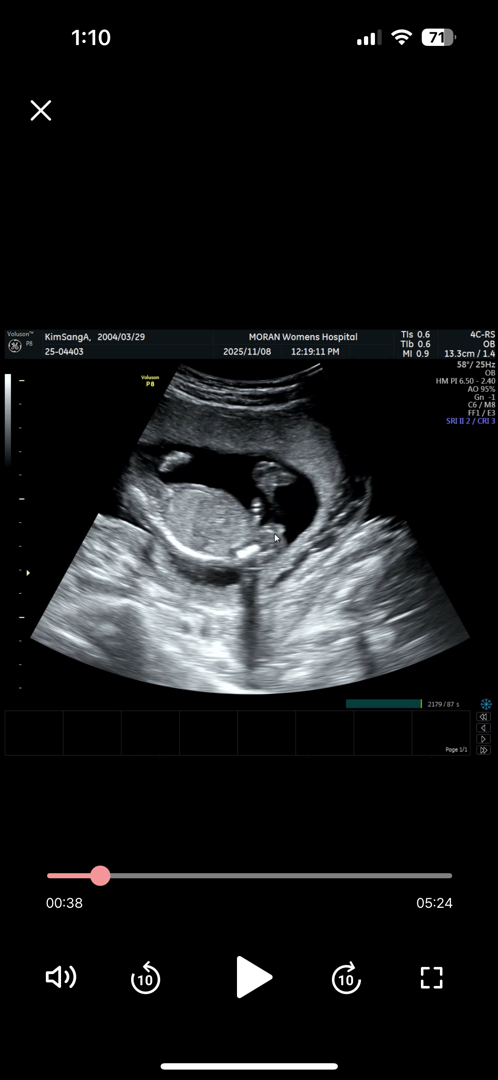

16주 성별 딸

안녕하세요! 16주여서 성별 확인하러 갔는데 딸이라구 하더라고요!! 혹시 16주때 성별 바뀔 확률이 어느정도 되나여?